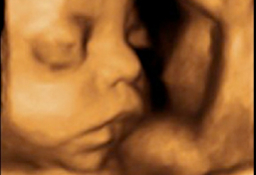

En la ecografía del tercer trimestre es muy difícil extraer una imagen completa del bebé. Rara vez se las apaña el ecografista para poder captar una "foto panorámica" de una criatura, que ya ocupa casi la totalidad del útero materno. Por eso, la mayoría de las ecos de esta edad gestacional se especializan en partes u órganos específicos del feto. El ecografista puede detectar aún ciertas anomalías del desarrollo, comprueba el líquido amniótico, el bienestar fetal y, muy importante, visualiza el cordón umbilical, que puede estar enrollado en algún órgano como cuello, pies o manos.